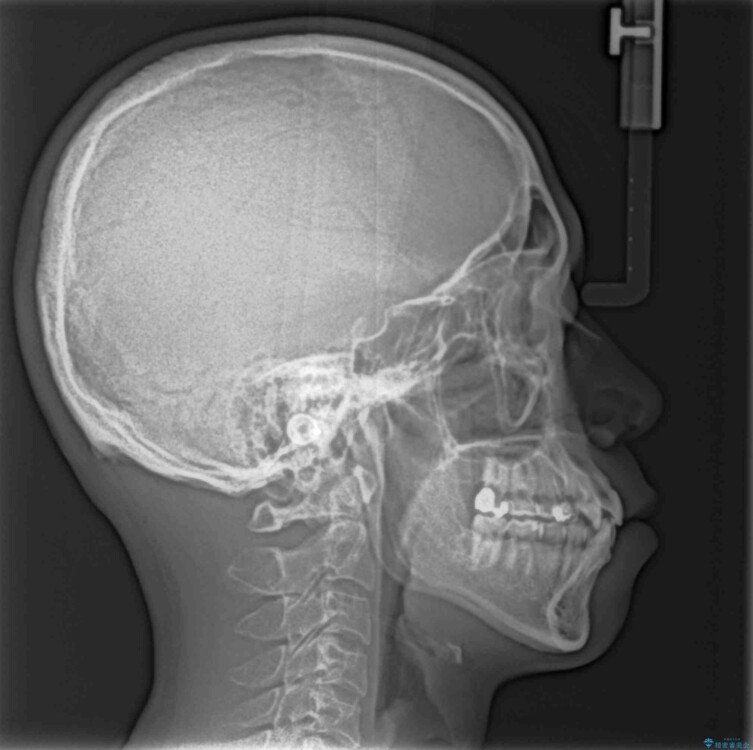

上下の前歯部に強い叢生(ガタガタの歯並び)があり、そのまま歯を並べると出っ歯になってしまう可能性がありました。

そこで、上下左右の第一小臼歯を抜歯し、歯が並ぶためのスペースを確保し叢生を解消する治療計画を立てました。

八重歯はきれいに整い、前歯もバランスよく収まり、横顔のラインも自然に改善されました。